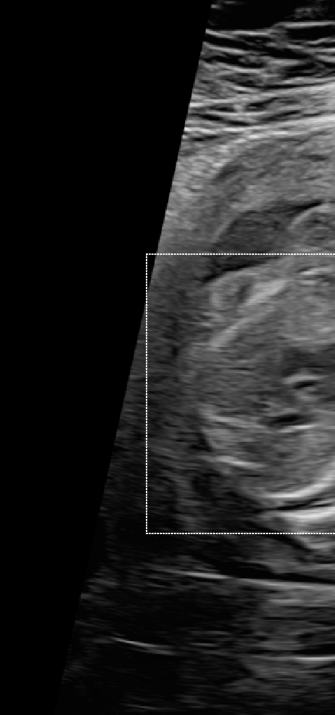

Three in vivo Bmode fetal images with and without aberration correction are presented in Figs. 10-12. GIF images of examples A-L (see Fig. 9 and Table 5) alternating between the corrected and uncorrected images are uploaded as supplementary material. The differences in image quality are easier to appreciate in the GIFs than in a side-by-side comparison. The data points for the three examples are colored black in Fig. 9. Table 5 give tabular values for the global sound speed estimate, sharpness increase (κ𝜅\kappa) and answers from the clinical evaluations.

Figure 12: Example C. In vivo fetal Bmode and coherence images using constant 1540 m/stimes1540dividemetersecond1540\text{\,}\mathrm{m}\text{/}\mathrm{s} and the estimated average sound speed map. The average sound speed map is shown in the top right corner and the rightmost colorbar indicates the sound speed values. Alternating GIFs are found in the supplementary material.

The in vivo examples A-C, in Figs. 10-12 respectively, show different nuances of how sound speed aberration correction improves focusing quality. A noticeable improvement in Fig. 10 is the improved contrast and clarity of borders. The sound speed correction seems to remove the double structure indicated by the arrows in Figs. 10c-10d. The skull border and the brain structures in Fig. 11 are also better defined and clearer after aberration correction. Example C in Fig. 12 is the image with the highest increase in Tenengrad κ𝜅\kappa, seen from Fig. 9 and Table 5. The improvement in image quality is evident around the boundary of the fetus body and the correction sharpens the structures indicated by the arrows. The improved contrast between the layers in the shallow tissue layers is also noticeable.